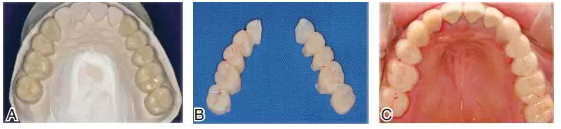

圖14根據(jù)診斷蠟型制作暫時冠戴入上頜。A.上頜后牙診斷蠟型;B.根據(jù)診斷蠟型翻制的暫時冠;C.暫時冠戴入口內

圖15下頜基牙初預備,在口內確定垂直距離,采取硅橡膠頜位關系記錄。將上頜通過面弓轉移上牙合架,確定上頜和顳下頜關節(jié)的關系,再通過頜位關系記錄,對合上下頜模型上牙合架

圖16雕刻下頜診斷蠟型(A),翻制下頜暫時冠并戴入口內(B)。調整咬合接觸,暫時冠戴用兩個月,患者無顳下頜關節(jié)和咀嚼肌系統(tǒng)不適,并能確認最適下頜位后,制作最終修復體